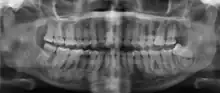

| Florid osseous dysplasia of the mandible | |

| Diagnostic method | X-ray, CBCT scan, vitality testing of teeth |

Cemento-osseous dysplasia (COD) is a benign condition of the jaws that may arise from the fibroblasts of the periodontal ligaments. It is most common in African-American females. The three types are periapical cemental dysplasia (common in those of African descent), focal cemento-osseous dysplasia (Caucasians), and florid cemento-osseous dysplasia (African descent). Periapical occurs most commonly in the mandibular anterior teeth while focal appears predominantly in the mandibular posterior teeth and florid in both maxilla and mandible in multiple quadrants.

Diagnosis is important so that the treating doctor does not confuse it for another periapical disease such as rarefying osteitis or condensing osteitis. Incorrect diagnosis could lead to unnecessary root canal treatments. It can be diagnosed by radiographic appearance. Confirming the tooth is vital, as is noting the demographic (African American females).[1][2][3]